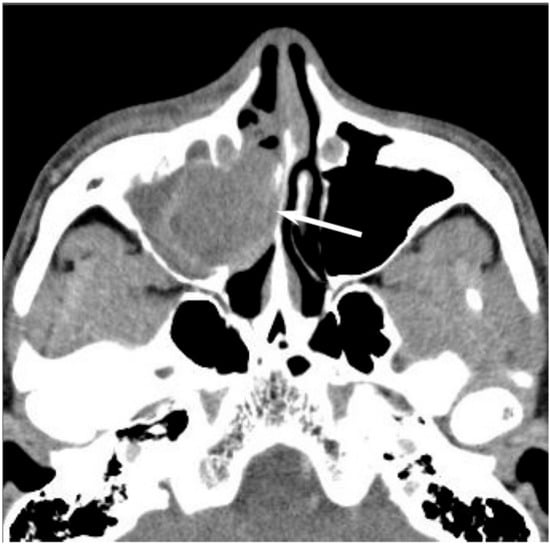

On CT, sinonasal lymphomas frequently show both infiltrative or permeative bony invasion and exhibit varying degrees of regional bony destruction [12]. NHLs with permeative-type tumor invasion typically cross the sinus wall and exhibit remnants of sinus wall as a linear structure within the tumor (Figure 5) [24]. In contrast, bony resorption or remodeling caused by the lymphoma may also be accompanied by bone sclerosis [25]. NHLs usually show isointensity on T1WI and slightly hyperintensity on T2WI [11]. Although the signal intensity of NHLs is nonspecific, the ADC measurement helps differentiate these tumors from other malignancies. In the maxillary sinus, the ADC values of NHL (0.61 × 10−3 mm2/s) were shown to be lower than those of SCCs (0.95 × 10−3 mm2/s), which reflects the greater cellularity of NHLs [12]. Although NHLs usually appear as a homogeneously enhanced mass, necrotic areas within the tumor are occasionally observed in NK/T-cell lymphoma [26,27].

Figure 5. Diffuse large B-cell lymphoma of the left maxillary sinus. Contrast-enhanced CT image showing a homogeneously enhanced lesion accompanied by remaining sinus walls as a linear structure within the tumor (arrows).